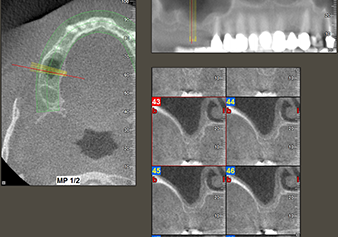

Une patiente de 49 ans, non fumeuse et sans antécédents médicaux remarquables, a été orientée vers notre cabinet de chirurgie orale pour l’extraction chirurgicale de la dent 16 préalable à la pose d’un implant. Après l’extraction, la patiente a rencontré de légers problèmes de sinusite, à la suite de quoi nous avons commencé par attendre six mois avant de prendre la mesure. À l’endroit prévu pour la pose de l’implant, l’os résiduel mesurait 3-4 mm de haut (Fig. 1 et 2).

Fig.2 : La DVT montre des dimensions adéquates sur chacune des vues axiale (gauche), latérale (dessus) et transversale (droite). La membrane du sinus maxillaire est encore légèrement épaissie.